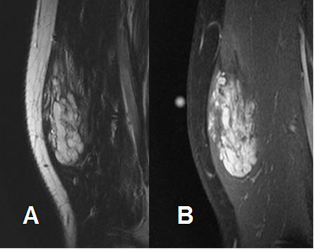

Fig 147. Hemangioma.

A: RM sagital en T2 y B: RM sagital en STIR. Imágenes serpentiginosas que corresponden a vasos dilatados, hiperintensos en ambas secuencias, en la parte anterior del muslo, por hemangioma.

Fig 148. Hemangioma

A: RM axial en T1 Simple y B: RM axial en T1 con contraste. Lesión hipointensa de tejidos blandos en la parte posterior del brazo. Presenta zona hiperintensa anterior, por contenido graso o sangrado subagudo y que realza con el contraste.

C: RM axial en T2 y D: RM axial en STIR. Lesión hiperintensa, con áreas hipointensas (Flechas), por el contenido de hemosiderina.